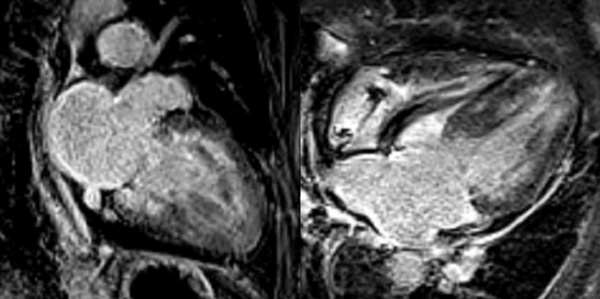

Figure 5 : Séquence Ciné-IRM

- Présence d’une hypertrophie ventriculaire gauche (HVG) asymétrique à prédominance septale mesurée au maximum à 23 mm.

- Visualisation de la sonde de PM avec artéfacts métalliques modérés au niveau du ventricule droit (flèches roses).

- Présence d’un épanchement péricardique de moyenne abondance (flèches rouges).